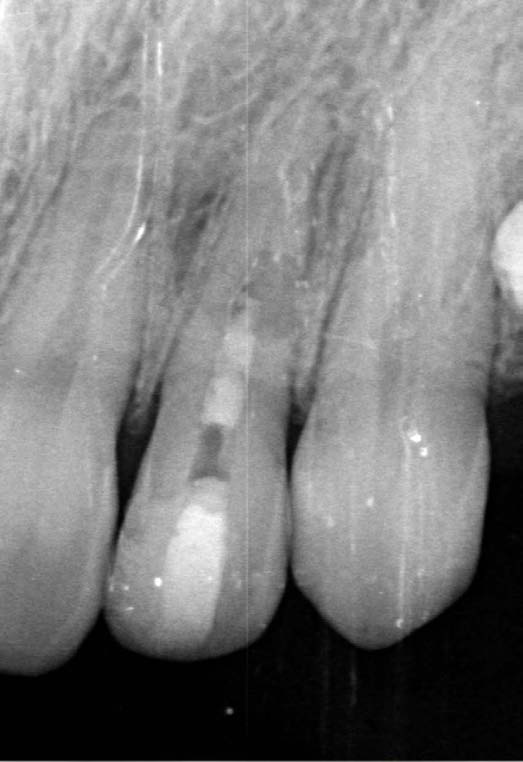

The X-ray snapshots showed signs of internal resorption in tooth 2.2.

The CBCT revealed intraroot perforating resorption on the vestibular root surface. In addition, a possible cause of resorption was identified as Oehlers' Type I invagination (1957), which was based on the radiological findings. According to the classification, Type I invagination is covered with enamel and is located within the coronal part, extending no further than the enamel-dentin junction. The authors believe that the infected invagination zone with subsequent creeping infection of the root pulp brought about the resorption. The response to the cold stimulus was very insignificant, especially in comparison with tooth 12. This made it clear that an irreversible destructive process is going on in the damaged tooth. Since the patient was planning orthodontic treatment and the resorption process could grow worse, it was decided to conduct endodontic treatment.